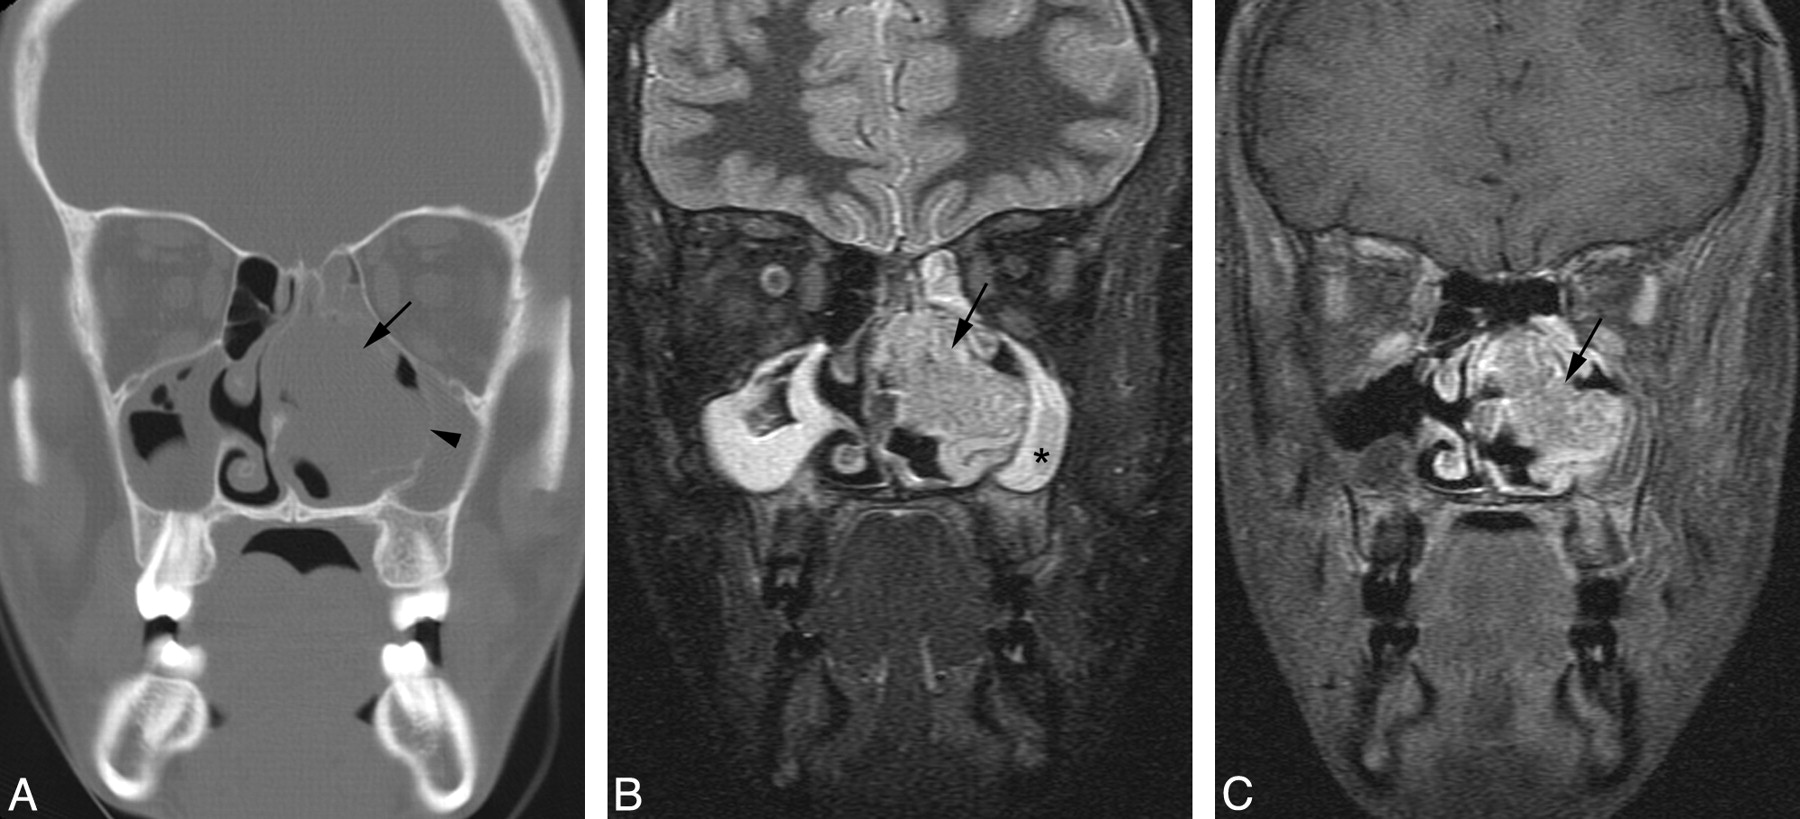

A 15-year-old adolescent boy presented with nasal obstruction and was found to have a nasal mass by an outside institution. Contrast-enhanced CT scan demonstrated a 40-mm × 29-mm × 29-mm lobulated, moderately enhancing mass arising from the left side of the nasal cavity. The mass eroded the middle turbinate and caused marked thinning and lateral deviation of the medial wall of the left maxillary antrum, and deviation of the nasal septum (Fig 3A). There was elevation of the inferomedial wall of the left orbit but no evidence of extension of tumor into the orbit. The tumor exhibited a relatively short T2 relaxation time but was hyperintense relative to muscle, with the pulse parameters used on the FSEIR images. It was hypointense compared with the trapped secretions in the ipsilateral maxillary antrum (Fig 3B). The tumor enhanced homogeneously (Fig 3C). The ipsilateral maxillary antrum and ethmoid air cells appeared obstructed. Biopsy results revealed undifferentiated carcinoma. Results of in situ hybridization for EBER were negative. Cytogenetic analysis revealed the following karyotype: 46,XY,+der(1)t(1;5)(p12;q11.1),−5,del(22)(q11q13).

Patient 3. Sinonasal carcinoma. A, Coronal CT scan of the sinuses reveals a tumor (arrow) arising from the left nasal cavity. The mass causes marked thinning and lateral deviation of the medial wall of the left maxillary antrum (arrowhead) and rightward deviation of the nasal septum. B, Coronal FSEIR MR imaging demonstrates that the tumor (arrow) is hypointense compared with the trapped secretions in the left maxillary antrum (star). C, Gadolinium-enhanced, fat-suppressed coronal T1-weighted MR image shows that the tumor (arrow) enhances homogeneously.